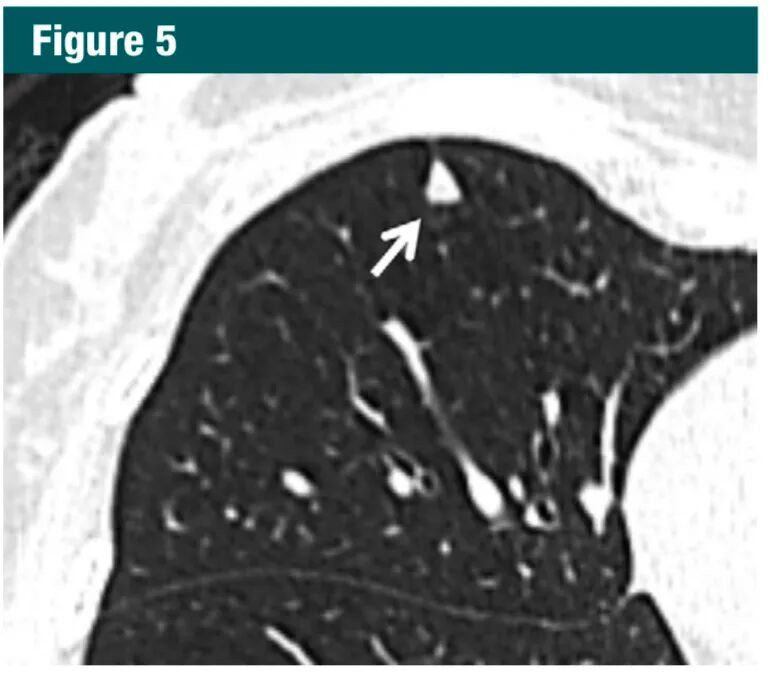

对于>8mm 的孤立实性非钙化结节,考虑3 个月后随访,作出诊断需要结合 PET 和 CT,组织取样,或选择上述方法的组合。需适当的依据大小、形态、伴随疾病和别的因素作出选择哪种方法(1A级:强烈推荐,高质量证据)。虽然 8mm 的实性结节的平均患癌风险仅仅为约3%,具体依赖于形态和位置,但在某些特定患者中,风险可以明显高于该百分比。当结节增大、它们的形态变得更加清楚,对其处理策略依据结节的表现较大小更为重要(图5-7)。因此,本指南包括了有创和无创的处理选择。

图片7Gc帝国网站管理系统

图片

图5-7

图5:CT显示胸膜下一三角形的实性结节(箭头),并有索条影伸向胸膜面,典型的肺内淋巴结。对于这种结节,不建议CT随访7Gc帝国网站管理系统